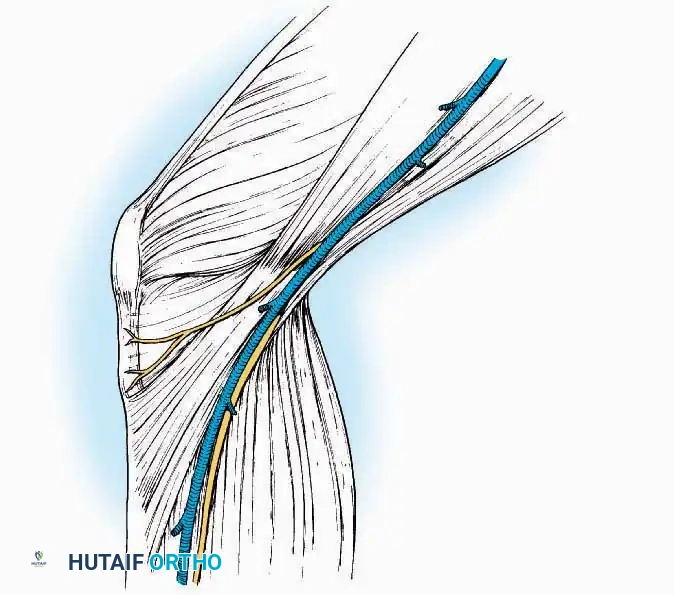

* Muscle Management: Identify the origin of the extensor digitorum brevis (EDB) muscle on the lateral calcaneus. Divide it in the direction of its fibers, or detach its origin entirely and reflect it distally to expose the subtalar and calcaneocuboid joints.

* Deep Exposure: Retract the extensor digitorum longus (EDL) tendons, the dorsalis pedis artery, and the deep peroneal nerve (DPN) medially. Incise the anterior ankle capsule to expose the tibiotalar joint.

* Tarsal Exposure: Expose the talonavicular joint by dissecting deep to the extensor tendons and incising its capsule transversely. Continue laterally through the capsule of the calcaneocuboid joint. By excising the fat pad within the sinus tarsi (lateral and inferior to the talar neck), the posterior facet of the subtalar joint is brought into direct view.